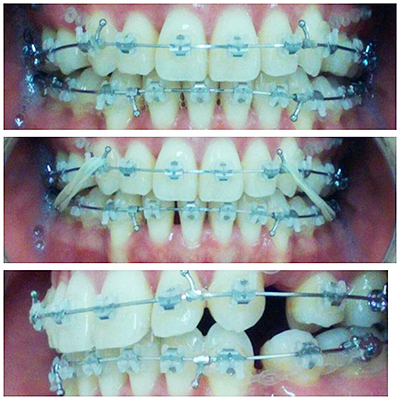

隙間がだいぶなくなってきて、後数ミリで閉じそうです。久しぶりにエラスティック(★印の写真)をやりましたが調整後二日間はかなり痛かったです。

今回ゴムが3本かかっているので馴れるまで話もしづらかったです。

全体的に咬合するようにエラスティックで優しい力を加えています。

下顎のブラケットポジションを変えました。ワイヤーも変わっています。

当たりが強い所もがなありますが、エラスティックで全体的に咬合するようになってきました。

今月からエラスティックを始めました。

ワイヤーやブラケットのフックにゴムをかけます。今回は歯を広げる事は終わったので噛み合わせをフラットにする為にやっています。

だいぶ全体的に噛み合わせるようになりました。エラスティックは食事と歯磨き以外は付けています。

エラスティックを始めて24時間程は痛みがありましたが、普通に話しもでき食事も食べられます。エラスティックは自分の努力次第なので、サボる事なくしっかりやるとその分、結果がでます!!私も毎日頑張っています(*´`*)

4回目の調整が終わりました。ワイヤーは一番太いワイヤーになりました。